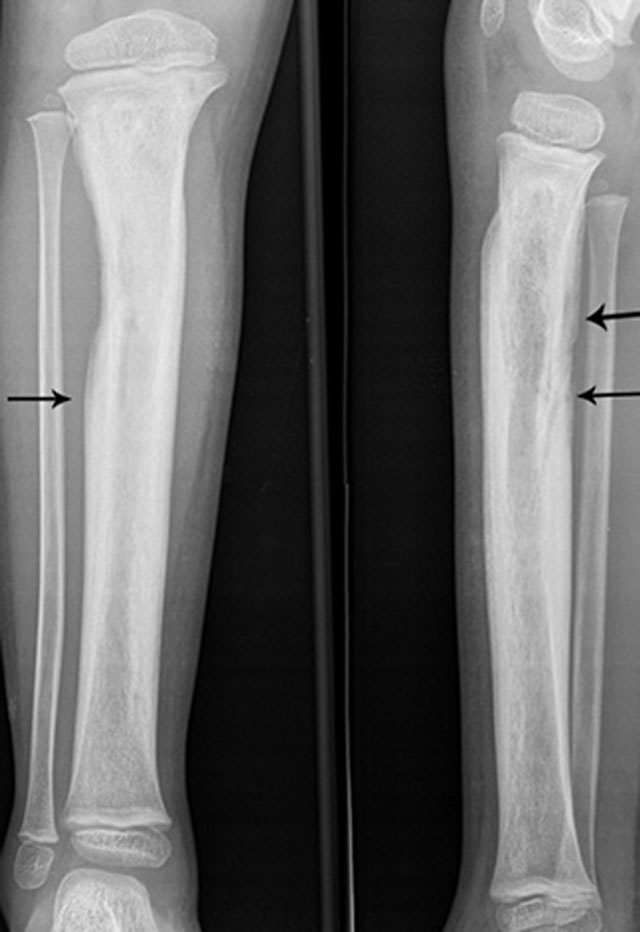

Figure 7

Extensive involucrum on plain radiography. Anteroposterior and lateral plain radiography showing extensive involucrum (arrow) at the tibial diaphysis (black arrows).